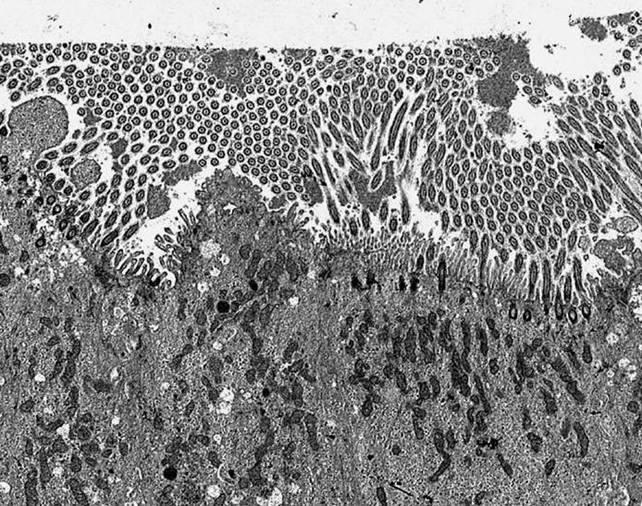

Primary Human Airway Culture

Michael Welsh and Tom Moninger